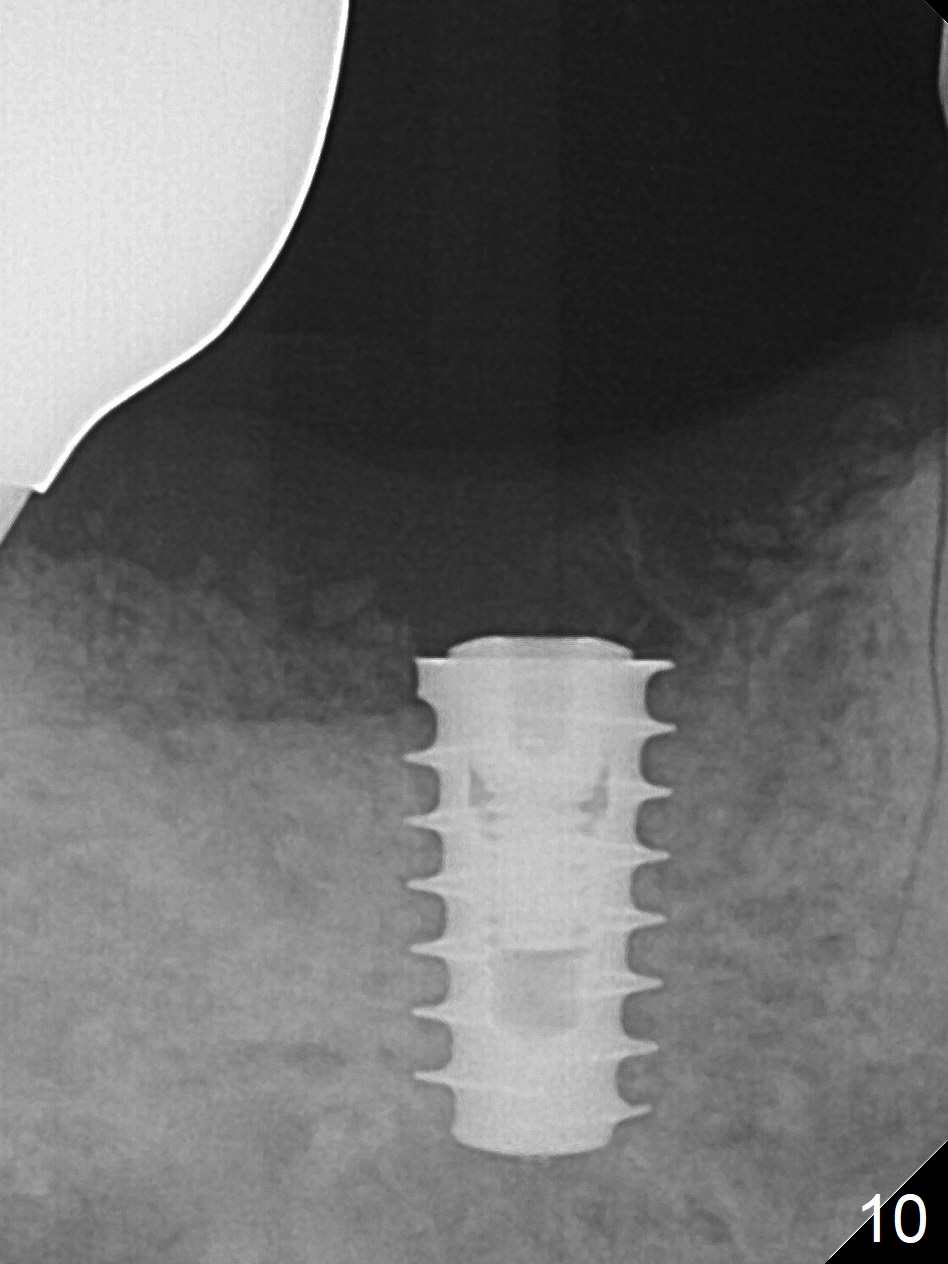

Extraction shows the large distal socket (Fig.1 D) and the thin and low septum (*) of the tooth #30. After Magic Split test confirms hard bone, osteotomy is initiated with 1.6 mm pilot drill with 11 mm stopper (Fig.2); there is 2.7 mm distance to the Inferior Alveolar Canal. Following Marking Bur, a 4.8 mm Magic Drill is used to finish the osteotomy with difficulty because of hard bone and ineffective local anesthesia due to infection. A 5x9 mm "dummy" implant is placed to determine the placement level relative to the distal crest (Fig.3 *). After removal of the dummy implant, an authentic one with the same dimension is placed with packing abundant allograft (.5-1.5 mm) and Osteogen (Fig.4 *); it appears that 4 to 5 threads (fins) of the implant (arrowheads) are engaged to the native bone for primary stability (>40 Ncm). Later more bone graft is placed distally (Fig.5 arrow). With the short implant placed not so deep, there is 6-7 mm clearance from the underlying canal (Fig.6). The patient is doing well 7 days postop (Fig.7). He feels that the provisional is too bulky buccally for the first 2 days postop. The buccal margin will be trimmed in another 2 weeks (dashed line). The patient in fact masticates on the right side postop. By the time he returns for provisional revision 1 months 10 days postop, he has mild pain. There is food entrapment. The provisional and the abutment are slightly loose, whereas the implant is stable with healing socket (Fig.8). A healing abutment is placed. The implant appears unstable nearly 5.5 months postop. The gap between the bone and implant seems to be large (Fig.9). The implant should have been larger and longer for fast healing. A healing screw is used instead. The site heals 10 months postop with an increase in bone density around the implant (Fig.10.) Prior to cementation of the final crown, the abutment is minimally exposed (Fig.11 (6.5x5.7(3) mm)). In fact the abutment screw becomes loose 2 months post cementation (1 year postop); it appears that crown/implant ratio is unfavorable (Fig.12). The implant is slightly placed mesially (cantilever). The patient cannot chew on the left. The tooth #19 is periodontally affected and the tooth #18 is missing. When bone loss is severe, the implant should be as large as possible and preferably tissue-level. The abutment screw is re-loosening 1.5 years post cementation (4 months post #19 socket preservation, Fig.13). The crown/implant ratio at #31 is more favorable than that at #30 (compare black lines). The crown at #31 has large contact area with the tissue-level implant (external), whereas the contact between the abutment and the bone-level implant is much less (internal). To prevent the abutment screw re-loosening (turning) in function, a screw driver (Fig.14 D) will be buried inside the crown/abutment after the screw is retightened. Make sure that the driver is in the middle of the access hole. Section the driver in situ obliquely (Fig.15); flat sectioning allows the driver to turn with the abutment screw in function. After insertion of plumber tape around the sectioned screw driver, use composite to fix the driver in place and seal the access hole (Fig.16). Occlusal check suggests weak link between the abutment and bone-level implant at #30.